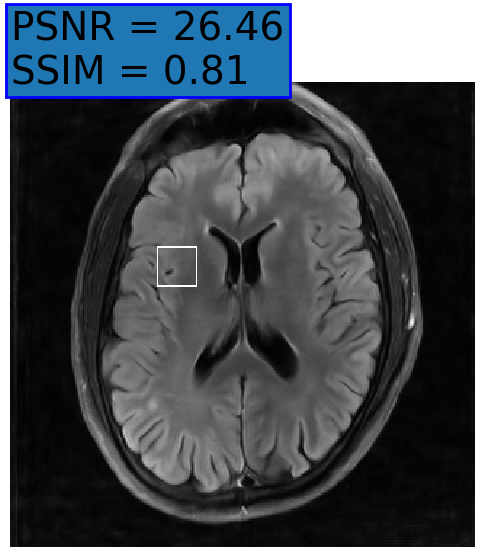

Figure 3: Reconstructions results. Rows 1 and 3: Examples of comparing the ground truth (GT) fully sampled image to the reconstructed images obtained by the three models (1-3), NPB-REC, baseline, E2E-VarNet trained with Dropout, and the NPB-REC std. map at accelerations R=4𝑅4R=4italic_R = 4, R=8𝑅8R=8italic_R = 8, respectively. Rows 2 and 4: The corresponding annotated ROIS of Nonspecific white matter lesions.

Fig. 3 presents examples of reconstruction results obtained by (1) our NPB-REC approach, (2) the baseline, and (3) Monte Carlo Dropout, for equispaced masks with two different acceleration rates R=4𝑅4R=4italic_R = 4 and R=8𝑅8R=8italic_R = 8. The reconstructed images predicted by the three models are smoother than the reference image. This is due to the fact that all the models were trained with SSIM loss, which tends to produce overly smooth reconstructions while preserving the diagnostic content and the anatomical features Sriram et al. (2020a). These images can be enhanced by dithering the image by adding a small amount of random Gaussian noise to produce a more textured reconstruction, as proposed in Sriram et al. (2020b).

Table 1 presents the mean PSNR and SSIM metrics, calculated over the whole inference set, for the three models. Our NPB-REC approach achieved significant improvements over the other methods in terms of PSNR and SSIM (Wilcoxon signed-rank test, pmuch-less-than\ll1e-4, except for SSIM values in line W, R=4𝑅4R=4italic_R = 4 where they are roughly the same for NPB-REC and Baseline). The improvement in the reconstruction performance can be noted both quantitatively from the metrics, especially for masks with acceleration rate R=8𝑅8R=8italic_R = 8, and qualitatively via the images of annotations, where our results show less smoothness than those obtained by Dropout.